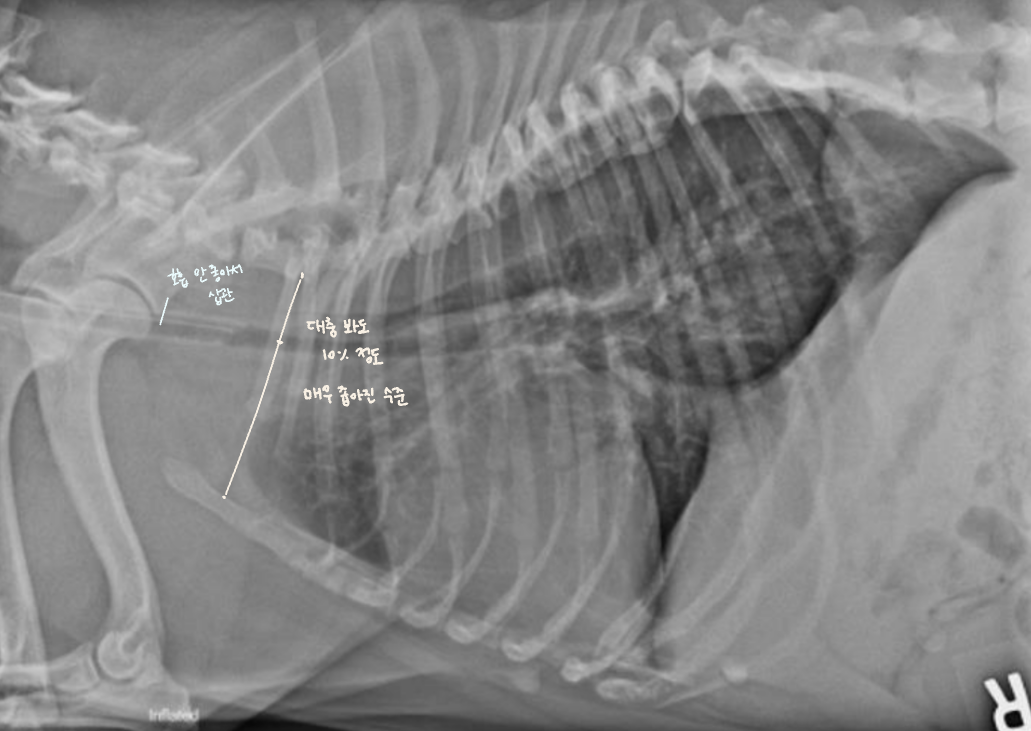

Tracheal diameter 재는 법법

• Thoracic inlet과의 비율로 나타낸다.

- T1의 끝부분에서, 1번 sternum의 가장 오목한 부분 (Thoracic inlet)을 선으로 잇고 길이를 잰다.

- Trachea의 길이를 잰다.

- 비율은 보통 0.2 정도.

(단두종에서는 정상적으로 더 작다.)